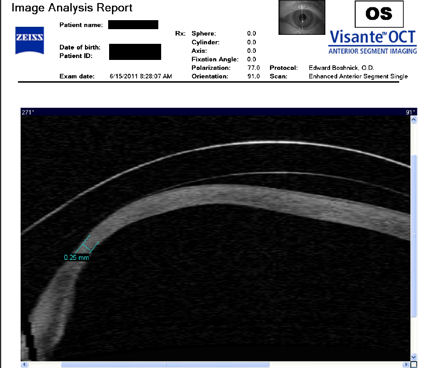

Следующие изображения были получены с использованием метода, называемого оптической когерентной томографией, или ОКТ. Прибор позволяет получить изображение в поперечном сечении путем сканирования передней части глаза (переднего сегмента) лучом света. Думайте об этом как об ультразвуке, использующем свет вместо звуковых волн для создания изображения живых тканей.

На снимке ниже показана роговица пациента, у которого после операции LASIK развилась эктазия. Пациент носит жесткие склеральные контактные линзы. Вы можете видеть выпячивание роговицы в самом слабом месте (эктазия), что приводит к сильному искажению зрения. Очки и мягкие контактные линзы неэффективны для таких глаз, как этот. Нажмите на изображение, чтобы увеличить.

Изображения любезно предоставлены доктором Эдвардом Бошником, который посвятил свою практику восстановлению качественного зрения и информации о эктазия после операции LASIK .